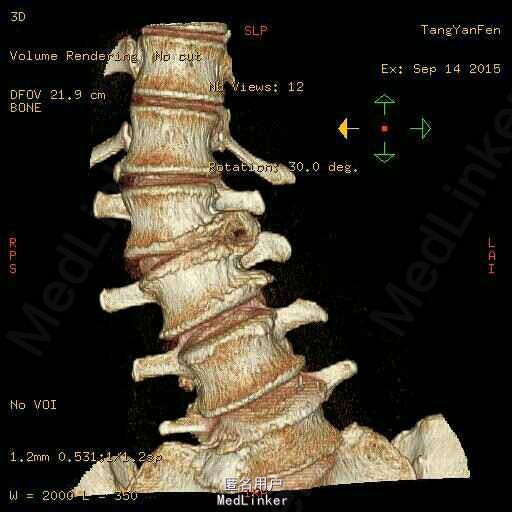

查体:脊柱侧弯,上肢无麻木,疼痛感觉异常,腰部右侧疼痛,右下肢及右臀部疼痛,麻木感。双侧肌力及肌张力可,膝腱反射(+),踝反射(+),病理征(—),直腿抬高试验。右侧40度,左侧55度。 辅助检查:腰椎x线片:腰椎侧弯,腰椎退行性改变,L5椎体略行前滑脱 脊柱全长:胸腰段呈S形,L5椎体向前滑脱,L3椎体略变扁,颈胸腰椎退行性改变 MRI:脊柱侧弯,L2-3,L3-L4,L4-L5,L5-S1椎间盘突出,相应节段椎管狭窄

诊断:腰椎侧弯,腰椎椎管狭窄 治疗:手术矫形:早期侧路减压融合,后期再行后路固定。

随访:病人初期手术时间段,术后恢复较快,病人神经压迫症状解除,腰部侧弯获得一定程度的矫正,术后起床用支局支撑后,可以下床活动,后期手术行后路经皮内固定。